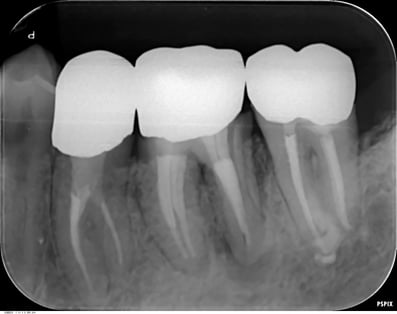

他院で抜歯と診断された症例です。友人の歯科医師の紹介で遠方から通院されました。初診時(左図)には、楔印で示すように、歯の根の先に黒い影が明瞭に写っています。が治療開始から8ケ月後(右図)では、黒い影は消えたり縮小しています。

歯の根の先の黒い影も消え(左図)、(手前は完全に消えていないが、完全な縮小傾向と症状がない)たので、クラウンを装着するための型採りをします。

右図の楔印は破折線です。破折線は特殊な方法で修復しています。

治療期間:約1年

治療回数:10回(1回/月)

治療費:29万円(根管治療+支台築造+セラミックス・クラウン)※毎回の処置料は別途

治療のリスク:他院では再治療ができないこと。